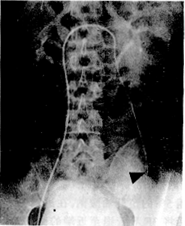

摘要 为了减少精索静脉曲张经皮硬化栓塞术中的复发因素,提高硬化剂治疗的效果,从1991年3月至1995年6月使用同轴插管方法,进行精索静脉远端主干和近端侧支血管的硬化栓塞,共治疗左侧精索静脉曲张23例,精索静脉近端插管全部成功,远端插管的成功率为78.0%,栓塞后的显效率为95.6%,无并发症。平均随访14个月未见复发。认为该方法可准确、安全、高效地进行精索静脉曲张的硬化治疗。

Abstract From March 1991 to June 1995,23 patients with left varicocele weretreated by percutaneous sclerotherapy with coaxial catheterization. Distal part andproximal collaterals of internal spermatic vein were occluded successfully in all patientswith no serious complication. Of 18 patients, the success rate of distal catheterizationhas been 78%. Varicoceles were greatly improved in 22 patients. Twenty-three patients werefollowed up for a period of 6~30 months and noreccurence has been found.